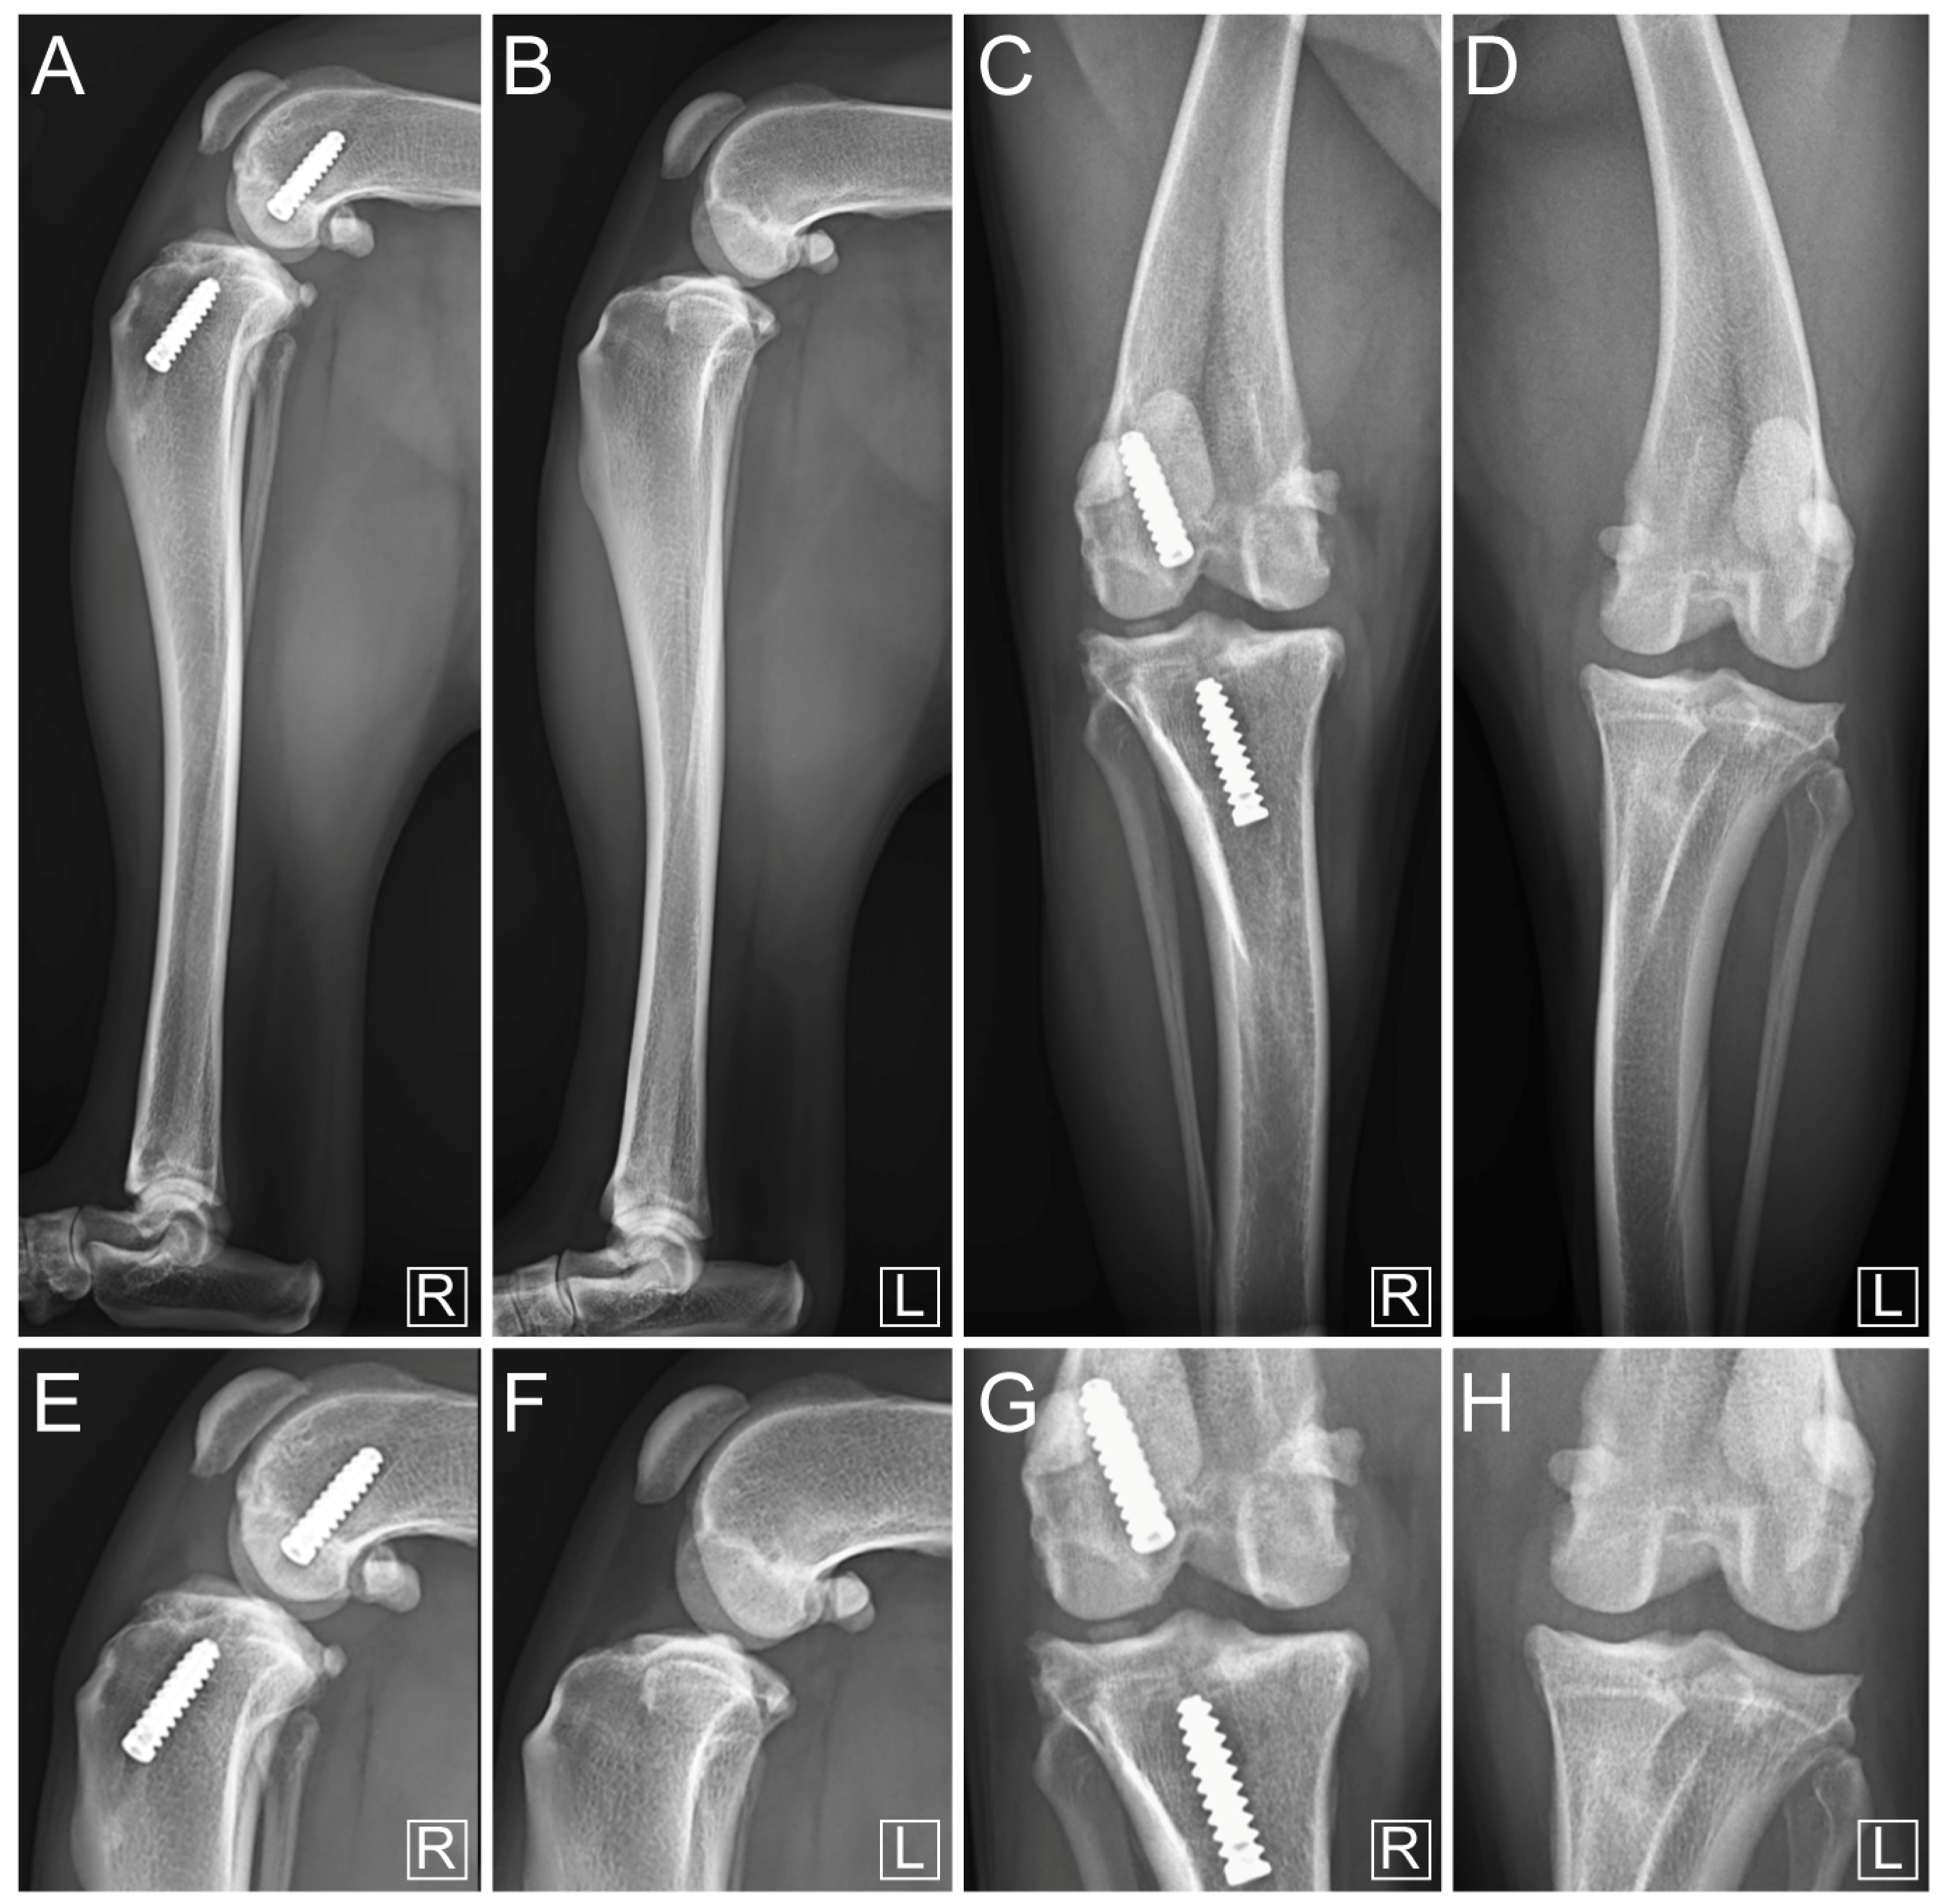

3. Results